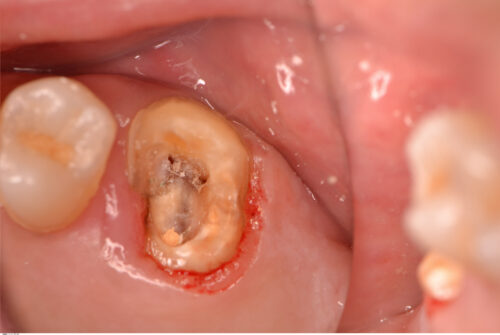

取れた詰め物は再利用できなかったので、患者さんには再度根管治療からやり直すことを提案し同意を得ました。根管口付近を慎重に探っていくと頬側根の入り口が見つかりました。

根管拡大が終わりました。ちなみに前医ではマイクロスコープを使って根管治療をしていたそうですが、患者さんのお話なので本当かどうかはわかりません。